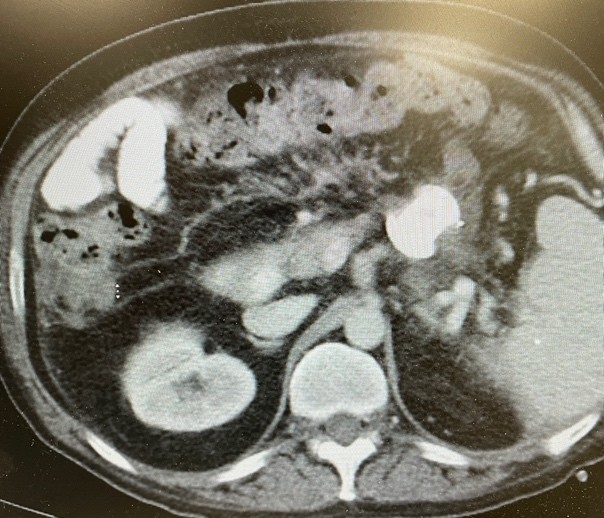

Figure 3. Necrotic tissue visualized through LAMS.

Figure 3